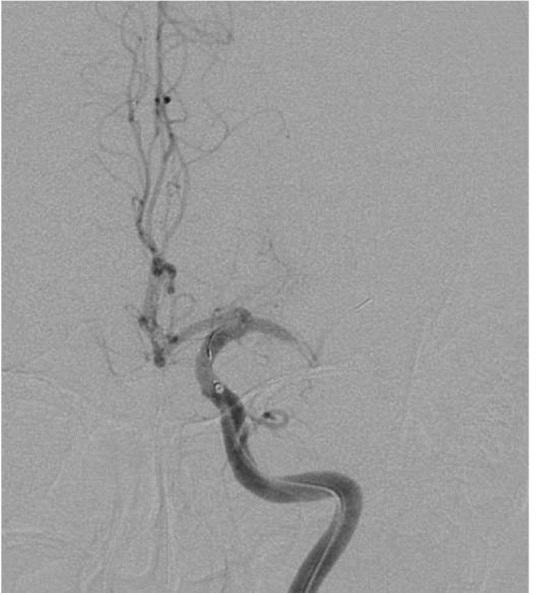

The optional endovascular approach for acute ischemic stroke is unclear. The Trevo stent retriever can be used as first-line treatment for fast mechanical recanalization. The authors developed a treatment protocol for acute ischemic stroke based on the assessment of clot quality during clot removal with the Trevo. This prospective single-center study included all patients admitted for acute ischemic stroke between July 2014 and February 2015, who underwent emergency endovascular treatment. According to the protocol, the Trevo was used for first-line treatment. Immediately after the Trevo was deployed, the stent delivery wire was pushed to open the stent by force (ACAPT technique). Clot quality was assessed on the basis of the perfusion status after deployment of the Trevo; continued occlusion or immediate reopening either reoccluded or maintained after the stent retriever had been in place for 5 min. If there was no obvious clot removal after the first pass with the Trevo, according to the quality of the clot, either a second pass was performed or another endovascular device was selected. Twelve consecutive patients with acute major cerebral artery occlusion were analyzed. Thrombolysis in cerebral infarction score 2b and 3 was achieved in 11 patients (91.7%) and 9 (75%) had a good clinical outcome after 90 days based on a modified Rankin scale score ≤ 2. Symptomatic intracranial hemorrhage occurred in 1 patient (8.3%). The overall mortality rate was 8.3%. Endovascular thrombectomy using the Trevo stent retriever for first-line treatment is feasible and effective.

急性缺血性卒中的选择性血管内治疗方法尚不清楚。Trevo支架取栓器可作为快速机械再通的一线治疗方法。作者基于使用Trevo取栓过程中对血栓质量的评估,制定了一种急性缺血性卒中的治疗方案。这项前瞻性单中心研究纳入了2014年7月至2015年2月期间因急性缺血性卒中入院并接受急诊血管内治疗的所有患者。根据该方案,Trevo被用作一线治疗。在部署Trevo后,立即用力推送支架输送钢丝以打开支架(ACAPT技术)。根据Trevo部署后的灌注状态评估血栓质量;持续闭塞或立即再通,在支架取栓器放置5分钟后要么再次闭塞要么保持通畅。如果使用Trevo首次取栓后没有明显的血栓清除,根据血栓质量,要么进行第二次取栓,要么选择另一种血管内装置。对连续12例急性大脑中动脉闭塞患者进行了分析。11例患者(91.7%)达到脑梗死溶栓评分2b和3分,90天后基于改良Rankin量表评分≤2,9例(75%)患者获得良好的临床结局。1例患者(8.3%)发生有症状性颅内出血。总死亡率为8.3%。使用Trevo支架取栓器进行一线治疗的血管内血栓切除术是可行且有效的。